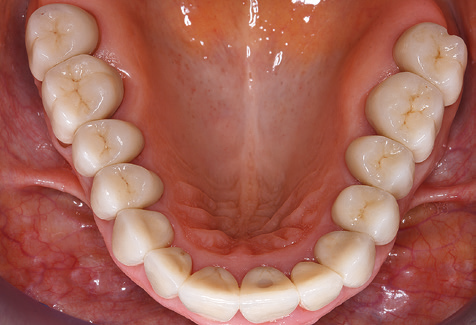

Following machine cleaning of the tooth and implant surfaces, the surfaces of the natural teeth are cleaned manually using standard hand instruments. When performing manual cleaning, particular attention must be given to maintaining the correct angle of application, appropriate sharpness, good support and working with the curette from apical to coronal. Either titanium or carbon curettes should be used for post-cleaning of the implant structures (Fig. 8). In addition to the use of ultrasonic devices, power jet devices can also be used in conservative dentistry. However, it must be taken into consideration that these procedures are not suitable for removing hard deposits and thus they cannot replace the use of hand instruments and ultrasonic instruments completely. In all cases, cleaning is followed by mechanical polishing of the accessible tooth and implant surfaces with polishing cups and polishing compounds (Fig. 9).